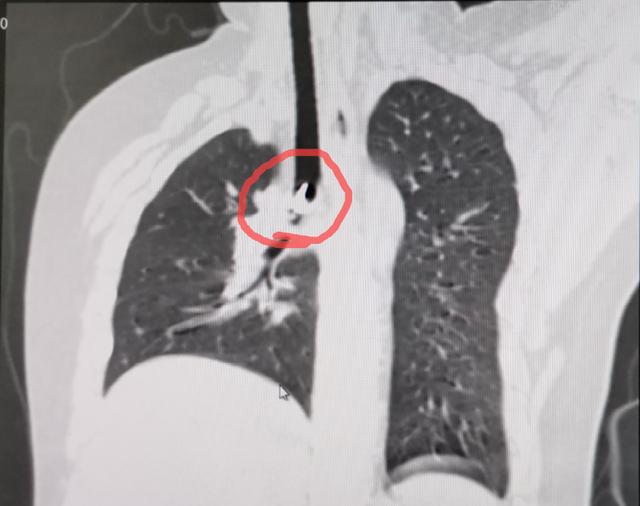

△ 肺部CT提示右主支气管开口处有异物

由于图钉尖锐,经新乡医学院第一附属医院儿童重症监护室和小儿内科三病区专家讨论,拟行支气管镜下异物取出术,PICU支气管镜团队成员李树军、王团结、王志远、任瑞娟密切配合,小心谨慎,顺利将图钉取了出来。